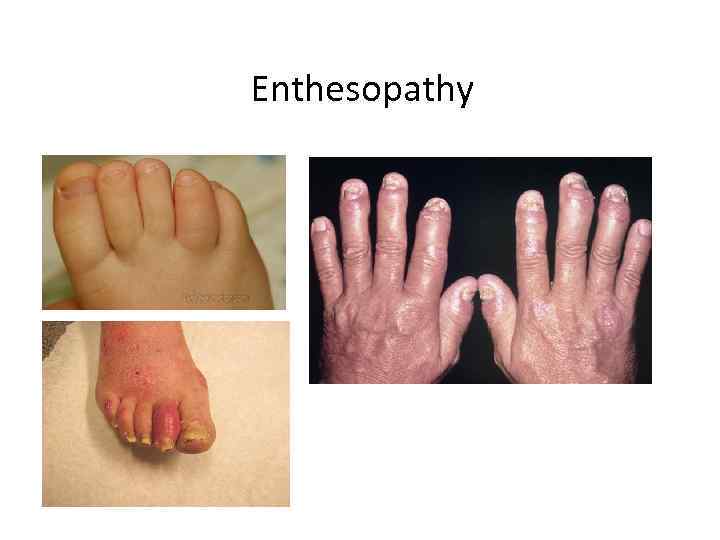

Enthesopathy